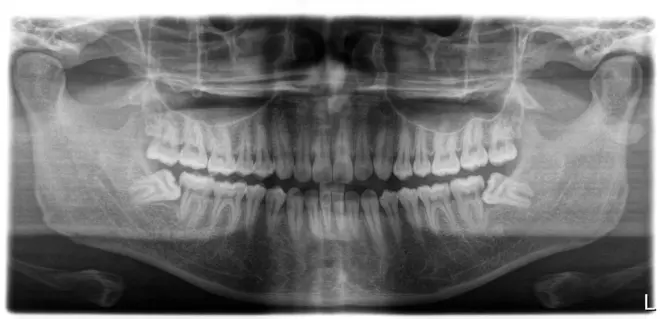

这是去年拍的照片

这是最近检查拔掉智齿后的情况